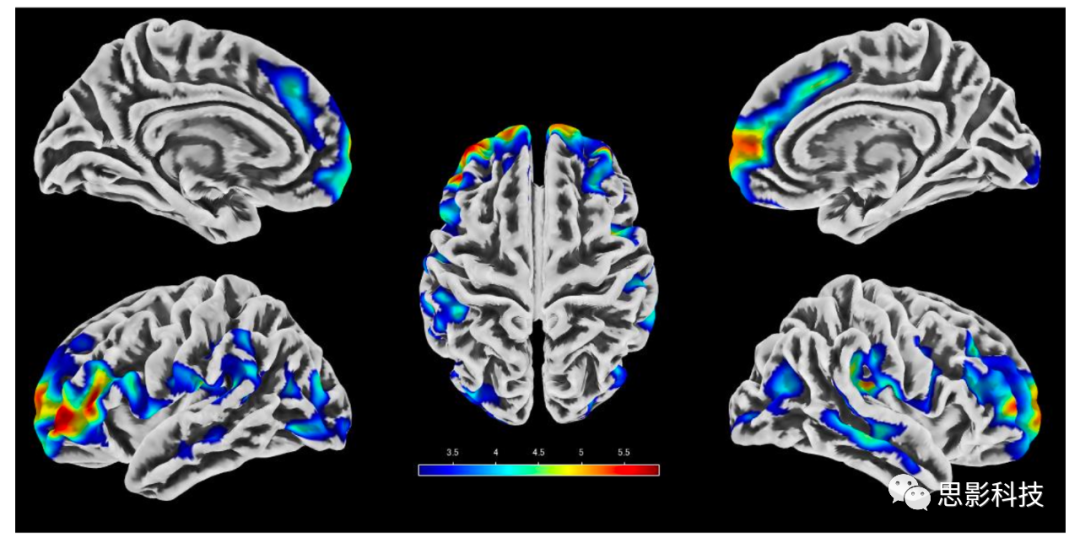

如圖1所示,VBM分析結(jié)果顯示在調(diào)整其他混雜因素后,糖尿病患者在以下腦區(qū)的灰質(zhì)損失比非糖尿病患者更顯著:雙側(cè)顳上回、右側(cè)顳中回、左側(cè)顳下回、右側(cè)額中回、雙側(cè)丘腦、右側(cè)尾狀核和右側(cè)小腦。蒙特利爾神經(jīng)研究所(Montreal Neurological Institute, MNI)坐標(biāo)顯示在補(bǔ)充表5中。與非糖尿病患者相比,糖尿病患者的大腦區(qū)域沒(méi)有顯示出灰質(zhì)區(qū)域的增加。與空腹血糖和2hPG水平呈負(fù)相關(guān)的區(qū)域如圖1所示,MNI坐標(biāo)顯示在補(bǔ)充表6中。與較高的空腹血糖水平相關(guān)的灰質(zhì)區(qū)域沒(méi)有顯著減少。相反,2hPG水平的升高與雙側(cè)上、中、下回、雙側(cè)顳葉、雙側(cè)腦島、左側(cè)頂葉島蓋、額下回右蓋部分和右側(cè)丘腦的萎縮有關(guān)。與較高的空腹血糖和2hPG水平相關(guān)的灰質(zhì)區(qū)域沒(méi)有明顯增加。

1. 與糖尿病(A)、空腹血糖(B)2hPG水平(C)呈負(fù)相關(guān)的灰質(zhì)區(qū)域。

糖尿病灰質(zhì)萎縮主要在雙側(cè)顳上回、右側(cè)顳中回、左側(cè)顳下回、右側(cè)額中回、雙側(cè)丘腦、右側(cè)尾狀回和右側(cè)小腦(A)。與較高的空腹血糖水平(B)相關(guān)的灰質(zhì)面積沒(méi)有明顯減少。與2hPG升高相關(guān)的腦區(qū)包括雙側(cè)上、中、下回、雙側(cè)顳葉、雙側(cè)腦島、左側(cè)頂蓋、右側(cè)額下回頂蓋和右側(cè)丘腦(C)。調(diào)整了年齡、性別、低教育程度、高血壓、血清總膽固醇、體重指數(shù)、吸煙習(xí)慣、飲酒、定期鍛煉、MRI腦血管病變、ICV/或降糖調(diào)節(jié)。